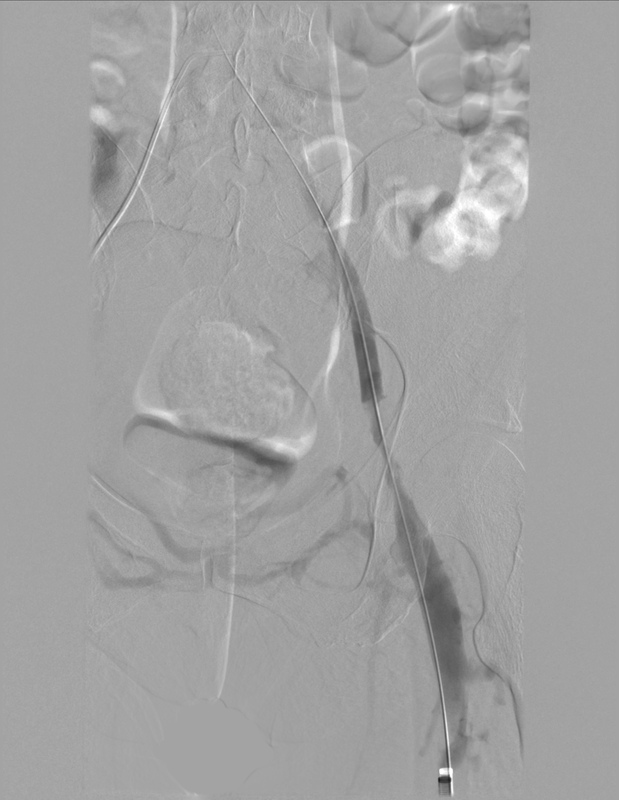

Figure 1

Representative angiographic images illustrating each grade of the proposed recanalisation scale

Grade 0: no recanalisation (completely occluded vessel);

Grade 1: partial recanalisation without spontaneous flow (flow only with compression);

Grade 2A: recanalisation with significant stenosis despite spontaneous flow;

Grade 2B: recanalisation without significant residual stenosis with spontaneous flow;

Grade 3: complete recanalisation with normal spontaneous flow and no residual thrombus or stenosis.

An optional “(S)” designation may be appended if stent implantation was used to enhance the angiographic outcome. Interobserver reliability was assessed using Cohen’s k statistic.